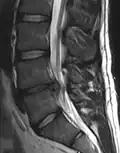

L'imagerie par résonance magnétique peut montrer la hernie, le canal vertébral, les nerfs, les tissus environnants. Les tissus mous sont les mieux analysés par cet examen qui est le plus performant pour le diagnostic de hernie discale. Les images pondérées en T2 montrent clairement la hernie.

IRM lombosacrée sagittale montrant une hernie discale de niveau L4-L5.

IRM lombaire sagittale montrant une hernie discale de niveau L4-L5.